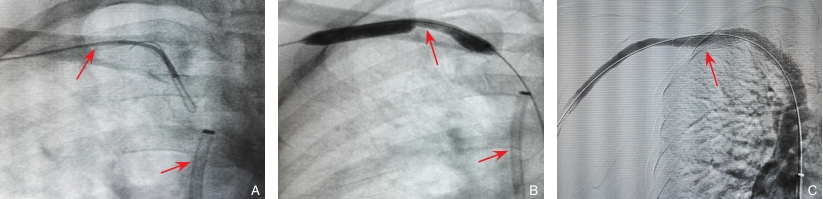

图1 经股静脉入路的UVA操作步骤 A:导丝进入右头臂静脉(brachiocephalic vein,BCV);B:PTA;C:PTS干预后造影确认静脉通畅Fig.1 Procedural steps of UVA via the femoral vein A: Guidewire advancement into the right brachiocephalic vein (BCV); B: PTA; C: Angiography after PTS confirming venous patency